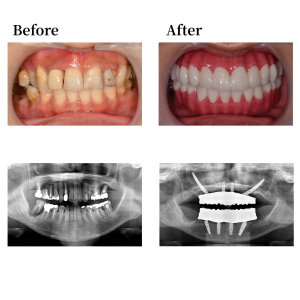

上顎骨の形状を整え、15、25の位置にザイゴマインプラントを45度傾斜埋入。12、22の位置にオールオン4インプラント0度垂直埋入。下顎も形状を整え、45, 35の位置にそれぞれオールオン4インプラントを30度傾斜埋入。 42, 32の位置に、0度垂直埋入。その後、マルチユニットアバットメントで角度補正を行い、プロビジョナルレストレーション(審美的な仮歯)を装着した。

上下顎はUTジルコニアで構成された、フルジルコニアブリッジでファイナルレストレーションとした。焼成されたジルコニアはステインテクニックで着色した。シェードカラーはA2。